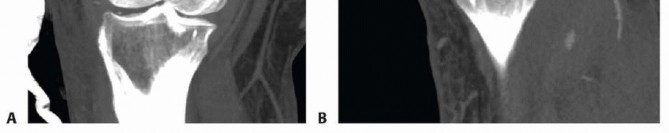

### FIG 9 • Critically ill elderly polytrauma Jehovah's witness patient with left C1 distal femur fracture. A,B. Initial injury AP and lateral views. C,D. Due to extremely low hematocrit, external fixation was the only surgical option allowed to minimize blood loss. Radiographs in bridging external fixation. The AP shows excellent alignment but the lateral shows the expected extension deformity secondary to pull of gastrocsoleus complex. E,F. After 5 weeks in an external fixator, AP and lateral radiographs show callus formation (red arrows). Patient is now cleared for definitive surgical intervention. Antegrade intramedullary nailing has been described and can be used for distal fractures with a large enough distal segment to allow for two locking screws. Malalignment has been a problem, as has adequate fixation. 4, 8 Retrograde intramedullary nailing can be used in the following cases ( FIG 10): All extra-articular type A fractures greater than 4 cm from the joint. This minimal length of the distal femur allows for multiplanar interlocking in the distal fragment. Type C1 or C2 fractures where the articular fracture can be anatomically reduced closed or with limited exposure. Percutaneous screws are used for the articular injury. Periprosthetic fractures around a total knee arthroplasty with an “open box” femoral component Most surgeons prefer to use a long nail, but short supracondylar nails are available as well. Multiple-hole short supracondylar nails have fallen out of favor. Plate fixation ORIF with plates can be used for all types A and C fractures but is ideal for the following injuries: Very distal type A fractures within 4 cm of the knee joint All articular type C fractures, but always for C3 types Periprosthetic fractures about a “closed box” femoral component of a total knee arthroplasty The partial articular type B1 or B2 if an antiglide plate is needed Plate options (preferred to least preferred; fixed-angle devices preferred) Fixed-angle locking plates (percutaneous jigs are advantageous and allow for minimally invasive techniques) Variable-angle (polyaxial) locking plates—allow for “fixed variable locking” within a defined range. It is useful for distal fractures and allows for increased screw 473 trajectories to gain additional locked fixation in short segments, which may not be feasible with fixed-angle trajectory plates ( FIG 11).

### FIG 10 • A,B. AP and lateral radiographs of an elderly patient with multiple comorbidities with an extra-articular distal femur fracture (AO type A; an incomplete intercondylar split— red dashed arrow). C,D. Postoperative radiographs showing stabilization with retrograde intramedullary nail. E,F. One-year postoperative radiographs showing a healed fracture with some subsidence of the metaphyseal region and mild protrusion of hardware through the notch. Ninety-five-degree condylar screw Ninety-five-degree blade plate Nonlocking plates with or without medial support (medial plate or external fixation) Limited internal fixation Limited fixation with screws only can be used for partial articular type B, especially type B3. The amount of open reduction required depends on the adequacy of closed reduction techniques and obtaining an anatomic reduction of the joint surface. Headless screws are useful for type B3 fractures in which the screws have to penetrate the joint surface ( FIG 12). Countersinking the screw heads can also be performed. Biomechanics of fixation: implant considerations There has been concern that the newer locking plate constructs are too stiff, resulting in inconsistent and asymmetric callus formation. 9 Some clinical evidence show less callus formation with stainless steel plates versus titanium plates. 9 Conversely, a biomechanical study has not shown a significant difference mechanically between constructs of stainless steel LISS plates with bicortical screws or titanium LISS plate with unicortical screws.1 474